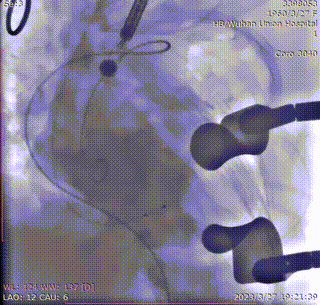

穿刺心尖,跨瓣。定位件进入窦部,造影确认:

将瓣膜降至合适平面,造影: